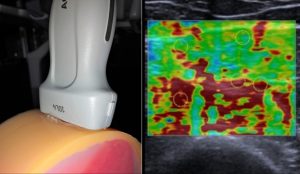

Jährlich sind weltweit Millionen Frauen von Endometriose betroffen, einer chronischen Erkrankung, die häufig mit Schmerzen, eingeschränkter Lebensqualität und Fertilitätsproblemen einhergeht. Die Diagnosestellung ist jedoch weiterhin herausfordernd und erfolgt häufig erst nach vielen Jahren. Moderne bildgebende Verfahren wie die Ultraschall-Elastographie ermöglichen die quantitative Bestimmung mechanischer Gewebeeigenschaften und können zusätzliche diagnostische Informationen liefern, da sich Endometrioseherde häufig durch veränderte Gewebesteifigkeiten auszeichnen.

Im Forschungsprojekt EndoKI wird untersucht, wie multimodale Bildgebungsverfahren und künstliche Intelligenz genutzt werden können, um die Diagnostik von Endometriose zu verbessern und patientenspezifische Modelle zu erstellen. Für die Entwicklung und Validierung elastographischer Messmethoden werden realistische Gewebemodelle („Phantome“) benötigt, die reproduzierbare und definierte mechanische Eigenschaften besitzen und typische Gewebekontraste der Erkrankung simulieren.